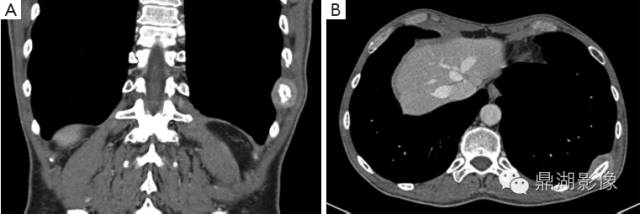

肾细胞癌骨转移

(六)肾癌骨转移 约23.5%发生骨转移,多见于股骨、肱骨、脊柱、骨盆、肋骨等处。常为单发,溶骨性破坏,骨干稍有膨胀,可侵蚀破坏骨皮质,发生病理性骨折。骨缺损区内有骨性间隔出现,颇似原发性肾肿瘤。也可为硬化型,或有广泛多层骨膜反应。